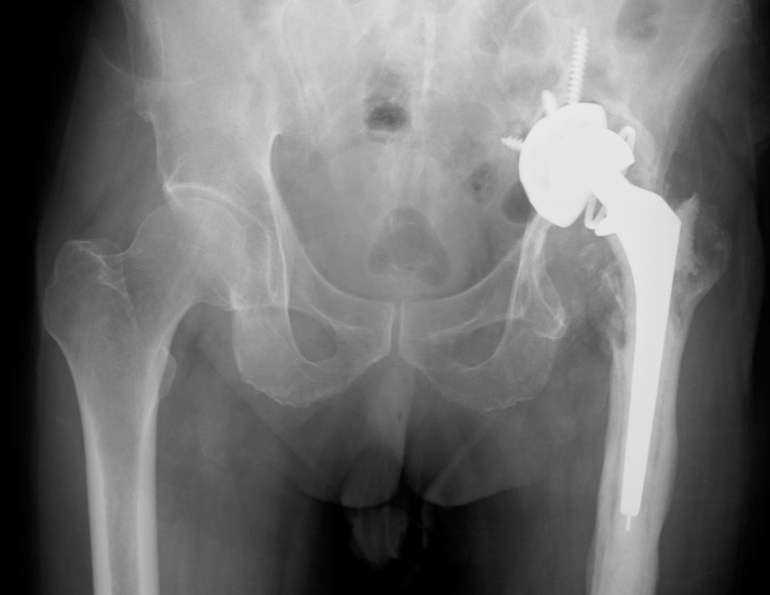

Pelvic X-ray of the patient with left hip pain.

On the X-ray, it is apparent that the left acetabulum has virtually been destroyed and the implant has actually entered the pelvic space. The left femur also looks both “moth-eaten” and hypertrophic, with new bone formation around the implant (compare with the right femur).

In this case, the patient has developed chronic left prosthetic hip implant infection. There was also a sinus tract which cannot be seen from the X-ray.